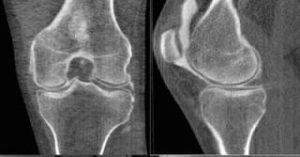

Рентгенография является основным методом диагностики гонартроза и позволяет определить:

• сужение суставной щели

• наличие остеофитов

• степень деформации сустава

КТ (компьютерная томография) назначается, когда необходимо:

• более точно оценить костные структуры

• выявить выраженные деформации сустава

• уточнить стадию заболевания при сомнительных данных рентгена

• подготовиться к оперативному лечению (оценка костной анатомии)

МРТ (магнитно-резонансная томография) применяется в случаях, когда требуется:

• оценить состояние хряща на ранних стадиях гонартроза

• выявить повреждения менисков и связок

• определить изменения мягких тканей и синовиальной оболочки

• уточнить причину боли при недостаточной информативности рентгена

МРТ позволяет детально визуализировать внутрисуставные структуры, а КТ — получить точную информацию о состоянии костных элементов сустава.